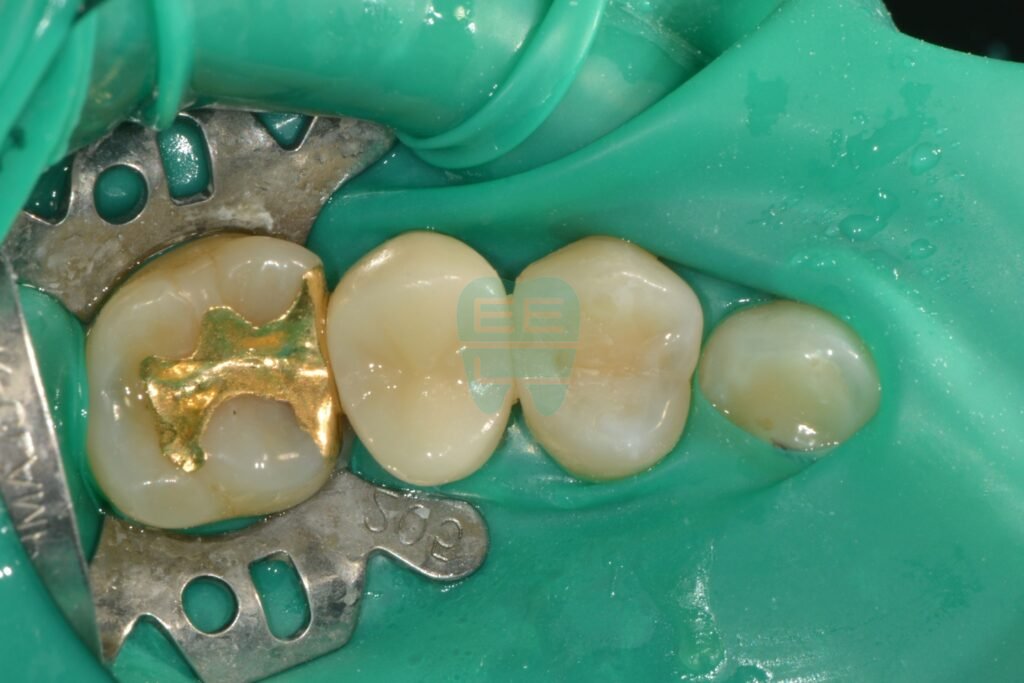

Minimally invasive caries removal complete — only decayed tissue removed

Minimally invasive caries removal complete

Here is the tooth after caries removal. If we had chosen an inlay restoration, we would have needed to widen the cavity significantly — grinding away healthy tooth structure to create access. But with resin build-up, that is unnecessary. Only the decayed portion is removed, with minimal tooth structure loss.